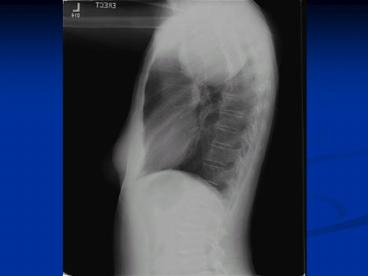

Mediastinal Benign Schwannoma

14